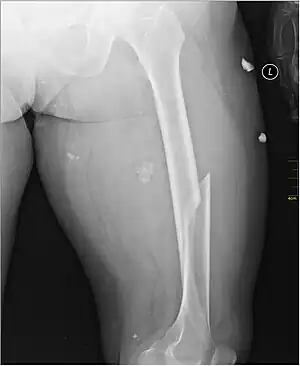

Radiography

Anterior-posterior (AP) and lateral radiographs are typically obtained.[4]

In order to rule out other injuries, hip, pelvis, and knee radiographs are also obtained.[5]

The hip radiograph is of particular importance, because femoral neck fractures can lead to osteonecrosis of the femoral head.[4]